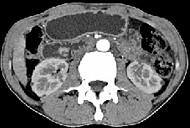

问题 男,48岁,进行性黄疸,发热,腹胀,影像检查如图,最佳的诊断是 ( )

选项 A、十二指肠乳头癌 B、胰头癌 C、胆总管结石 D、胆总管癌 E、胆总管囊肿

答案 A